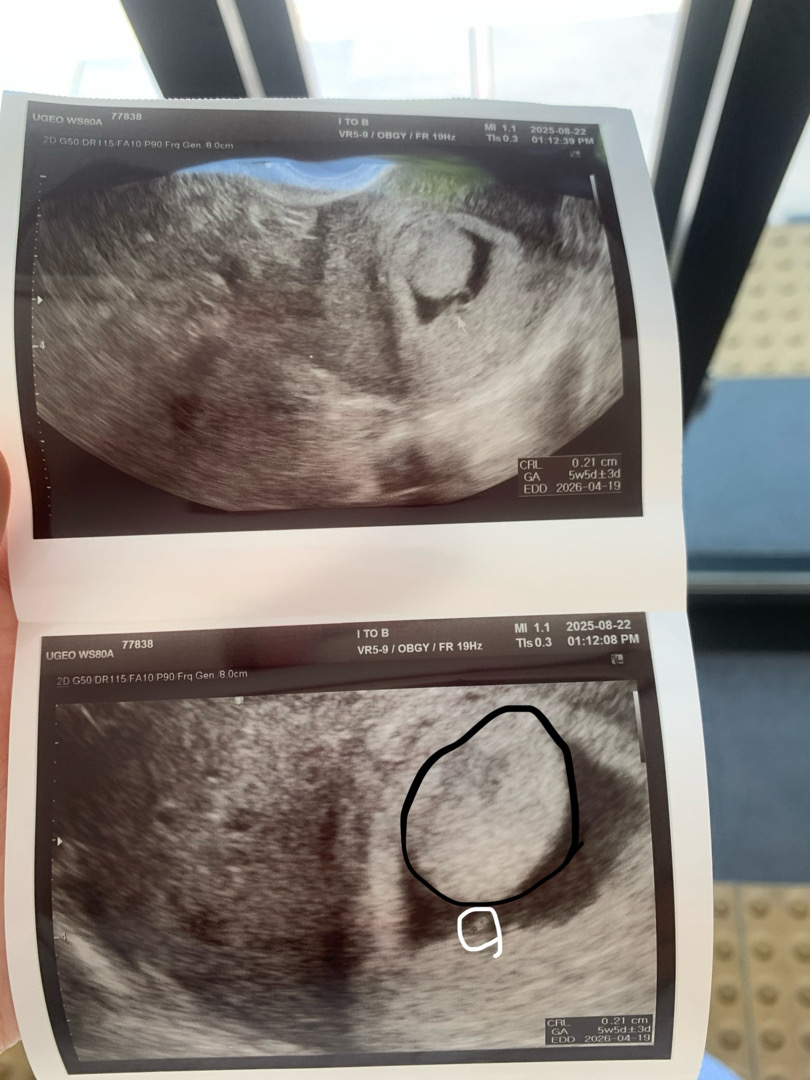

초음파사진좀 봐주세요ㅠㅠ

6주0일이에요 아기는 2mm 정도 이제 막 보이기시작했고 하얀 동그라미가 아가래요 근데 태반? 검정색동그라미부분이 태반이라는데 저번주엔 두개로 나눠져서 보였는데 저번주에도 크기는 컸지만 신경안써도 된다그러셨어요 이제 아기만 보이면된다고 오늘 아기는 보였는데 태반이 두개가 한덩어리가됐고 저렇게 커졋어요 의사선생님도 너무크다고 좋은징조는 아니라고하셨어요 그렇다고 저거때문에 유산이된다거나 그런것도 없대요 그냥 지켜봐야만한다고 지금은 아기만 보면된다고 하셨는데.. 태반? 저게 저렇게 클수가있나요ㅠㅠㅠㅠ 자궁도 잘 커지고있다는데.. 초음파모양이 다른사람들이랑 달라서 걱정되네요ㅠㅠ

6주밖에 안됐는데 태반이 저렇게 큰 건 처음 보네요... 초음파를 다시 찍어보시는 건 어떨까요?

엥.... 6주차에 태반이 저정도로 발달한다구요...? 그 주수면 난황 확인, 아기도 겨우 보이고, 갈수록 난황 크기 줄어들며 점차 태반이 큰다고 들었는데... 아무리 봐도 태반이란 생각은 안 들어요.